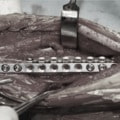

Advanced Locking plate system と Locking compression plate system

当院ではAdvanced Locking plate system(ALPS)と、Locking compression plate system(LCPS)という骨接合法で骨折症例の治療を行っています。

Locking Compression Plate

LCPは、スクリュー(ネジ)とプレート(金属の板)をロックする特殊な構造により骨折部位を固定する新しい世代のプレートシステムです。ひとつのホールでロッキングスクリューとスタンダードスクリューの使用を選択できるユニークな構造をしているため、骨折断端間の圧迫を目的とした従来型プレート固定法に加え、高い角度安定性を有するロッキングスクリューを用いた固定法の選択が可能です。従来のプレートシステムでは困難だった部分の骨折や癒合不全の症例に高い治療効果をもたらします。

Matrix MANDIBLE

AO/ASIFコンセプトのもとに解発された人医用のロッキングプレートシステムです。材質がチタン製で、10°〜15°の角度をつけてロッキングスクリューの設置が可能であり、制限された部位での強固な固定に優れています。